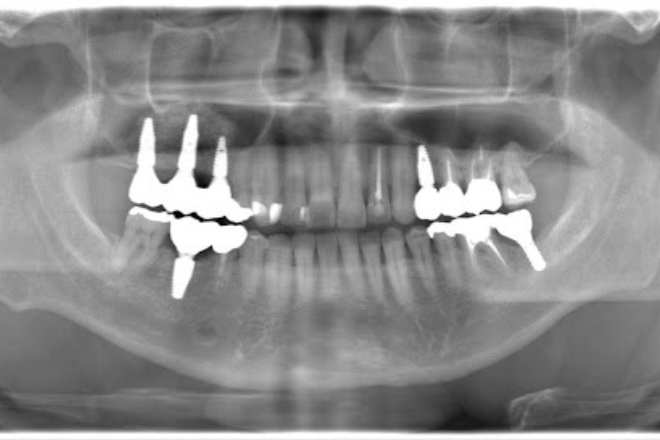

インプラント治療の成功率を高めるには、歯科用CTによる立体的な画像診断が欠かせません。

骨の厚みや神経の走行を三次元データで正確に把握することで、経験や勘に頼らない客観的な治療が可能になります。

先進的な歯科用CTとシミュレーションソフトで、顎の骨や神経の位置を立体的に把握し、正確な埋入位置を診断することが可能です。